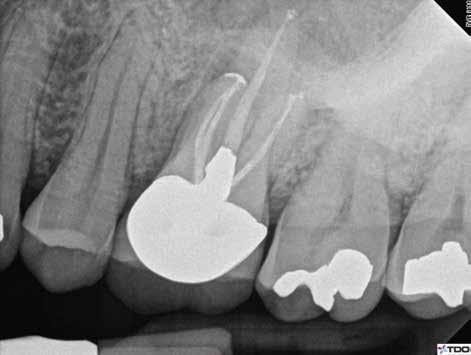

1. a–g. ábrák: A direkt pulpasapkázás lépései. Kiindulási bitewing-felvétel: A meglévő restaurátum közel helyezkedett el a pulpakamrához (a). Kiindulási periapicalis felvétel: Nincs periapicalis elváltozás fennállására utaló jel (b). A pulpaexpozíció (c). A vérzéscsillapítás céljából 20 másodpercen keresztül steril vattagombóccal történő kompressziót követően látható pulpaseb (d). A pulpasapkázás céljából behelyezett anyag, a széli részek tisztázása előtt készült felvétel (e). A röntgenárnyékot nem adó ideiglenes tömés behelyezése után készült felvétel (f). Az első ülés végén a röntgenárnyékot nem adó ideiglenes töméssel ellátott fogról készített röntgenfelvétel (g).

2. ábra: A hat hónapos kontroll alkalmával készített röntgenfelvételen vastag dentinhíd látható a pulpasapkázó anyag alatt.

3. ábra: A hároméves kontroll alkalmával készített röntgenfelvételen megfigyelhető a restaurátum pontos illeszkedése.

A kezelést követően a beteg tünetmentes volt. A kérdéses fog a kontrollvizsgálatok során végzett szenzibilitástesztekre fiziológiás reakciókat adott. A hat hónapos kontroll alkalmával készített röntgenfelvételen a sérülésnek megfelelően széles dentinhidat észleltünk (2. ábra). A restaurátum a hároméves kontroll során is megfelelőnek bizonyult (3. ábra)